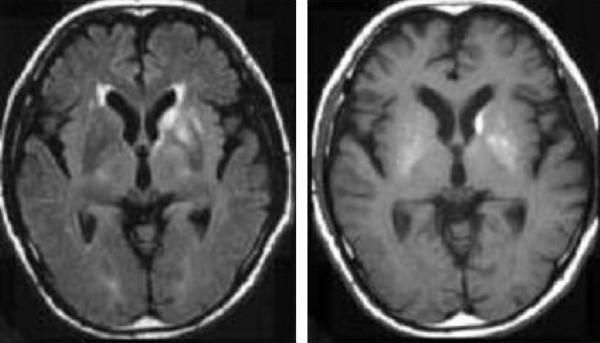

Nhồi máu bán cấp thường ngấm thuốc tương phản [9-12]. Trong giai đoạn này, cộng hưởng từ khuếch tán có thể không đủ khả năng để phát hiện nhồi máu, bởi vì sự bình thường hóa giả của hệ số khuếch tán biểu kiến (apparent diffusion coefficient) có thể che giấu hình ảnh nhồi máu [8,9]. Mức độ ngấm thuốc tương phản ít trong giai đoạn này của nhồi máu có thể gây khó khăn [9,12]. Một nốt ngấm thuốc kích thước nhỏ ở vỏ não hoặc ở vùng dưới vỏ có thể xuất hiện và giả di căn não (Hình 2 và 3) [9]. Chứng loạn nhịp tim (arrhythmias), là nguồn gốc chủ yếu của cục nghẽn mạch não, các nhồi máu não giai đoạn sớm, và bệnh tim thiếu máu cục bộ thường được phát hiện ở các bệnh nhân này. Nhồi máu bán cấp ngấm thuốc không đều có thể giả một glioma bậc cao (Hình 4 và 5), nhưng sự khu trú ở vùng phân bố của động mạch xiên hoặc tình trạng ngấm thuốc của các nếp cuộn não hoặc ít hay không có hiệu ứng khối là tính chất của nhồi máu bán cấp [12].

Hình 3 a/b. U di căn nhỏ xuất hiện đột ngột? Bệnh nhân nam 58 tuổi xuất hiện đột ngột liệt nhẹ nửa người phải và thất ngôn trong khi đang uống rượu. (Chẩn đoán cuối cùng: một ổ nhồi máu nhỏ thêm vào ở giai đoạn bán cấp)

a -c : MRI lúc nhập viện

a: Nhồi máu não cấp được biểu thị dưới dạng một vùng tăng cường độ ở vùng thái dương đỉnh trên ảnh fast SE T2-W (2500/90)(*).

b: ảnh SE T1-W (600/15) sau tiêm thuốc đối quang từ cho thấy một vùng cường độ tín hiệu thấp không ngấm thuốc với mạch máu nổi rõ ở rãnh não (mũi tên).

Hình 3 c/d.

c: một nốt nhỏ ngấm thuốc (mũi tên) ở vỏ não đỉnh phải trên ảnh SE T1-W (600/15) sau tiêm thuốc.

d: ảnh SE T1-W (600/15) tiêm thuốc đối quang sau 3 tháng. Tổn thương nhỏ ngấm thuốc ở vùng vỏ đỉnh phải đã biến mất.